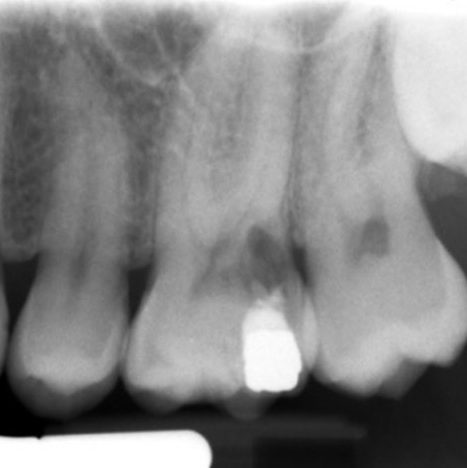

Figure 5: From the PA radiograph LR5 has the classical appearance of internal resorption.

However, the CBCT scan shows the resorption is external cervical resorption.

The resorption starts buccally at the cervical margin. It extends down the root and spreads 360º around the root canal.

We often see this appearance because the canal is surrounded by a protective predentine layer, which is more resistant to resorption